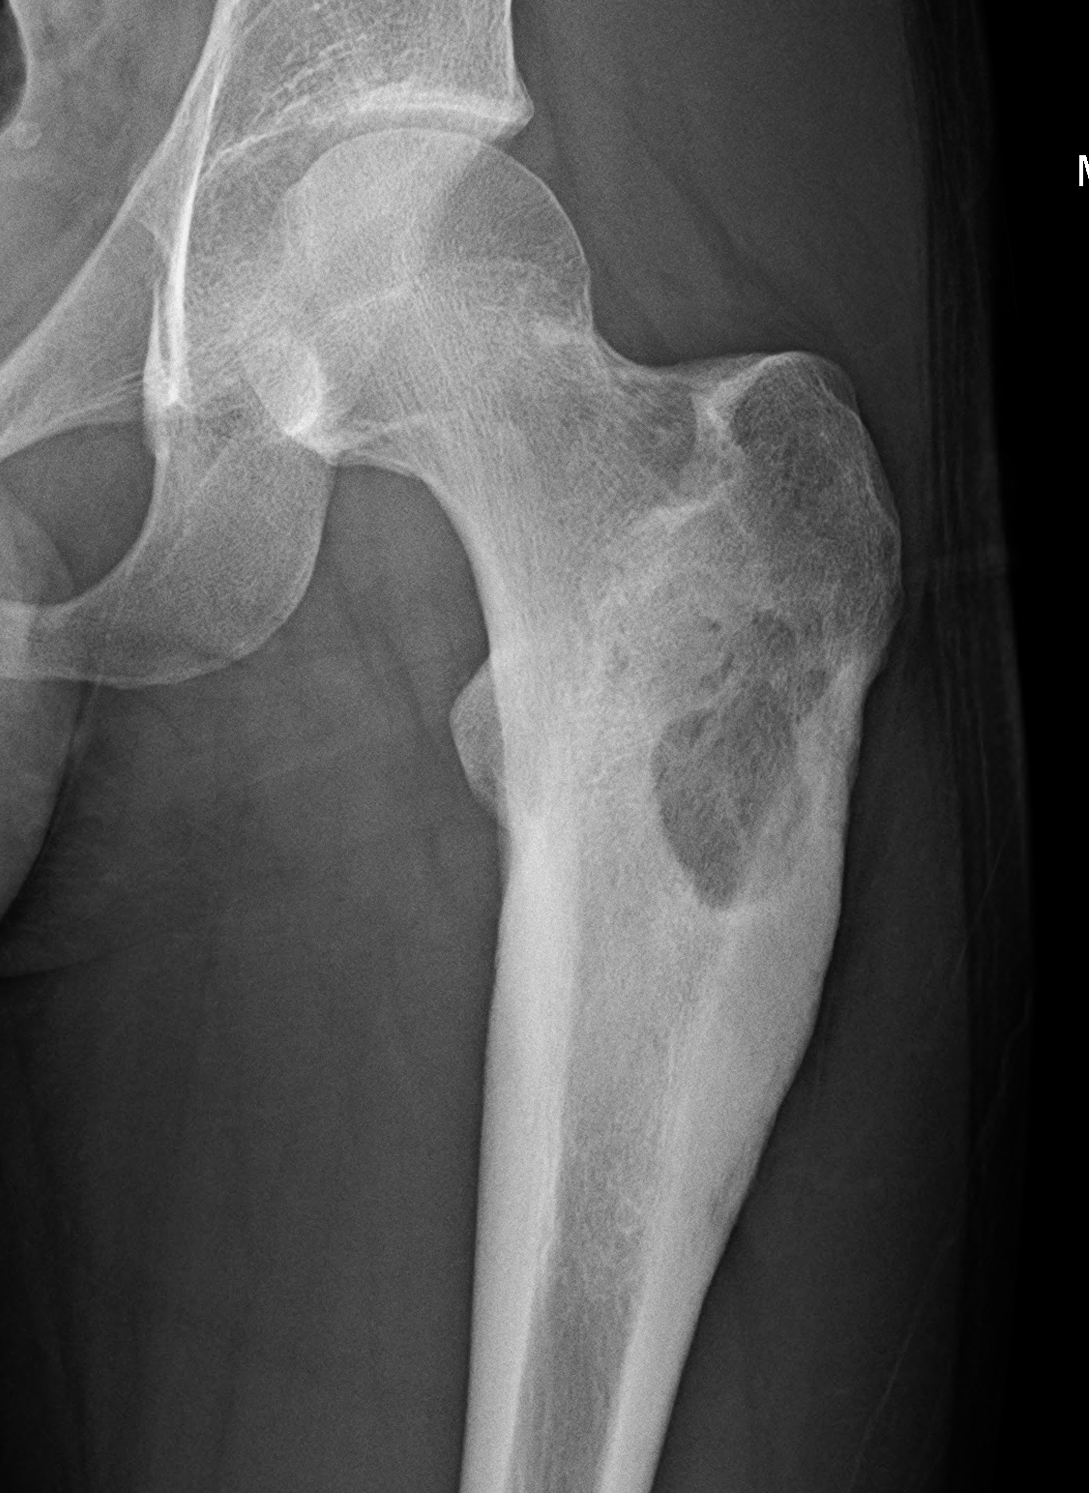

L'osteoblastoma è un tumore delle ossa che si localizza solitamente alla colonna vertebrale.

Il tumore è generalmente benigno, anche se esiste una forma più aggressiva.

La lesione interessa l'area corticale, piuttosto che la midollare, ed è prevalentemente sclerotica.